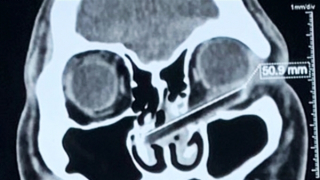

Bị kẻ ngáo đá dùng đũa đâm xuyên hốc mắt